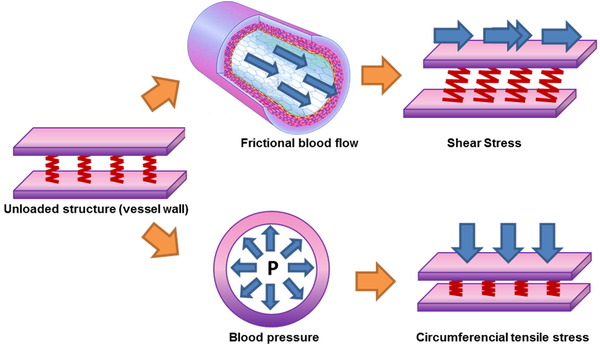

1.1 Biomechanical forces

It is well-known that the interactions of pulsatile blood flow with arterial geometries generate complex biomechanical forces on the vessel wall with spatial and temporal variations [1]. Those biomechanical forces act over the internal layer of the arteries, endothelium. The endothelium produces a wide array of biochemical signals (homeostatic mediators) under physiological conditions [2][3] keeping the artery healthy. A key stimulus to maintain the protective status of the endothelial lining at the inner vessel wall is the tangential force that blood flow exerts on it; this tangential force is known as wall shear stress (WSS) (see figure 1). Fluctuations of the wall shear stress provoke changes in the biochemical signals[4], may arise the initiation and progression some cardiovascular diseases. For example, the growth or possibly rupture of the aneurysm wall[5], plaque instability in the carotid bifurcation[6][7] or in the coronaries [8][9], thrombus formation[10][11] or playing an important role in atherogenesis[12][13]. From a clinical stand point, the assessment of hemodynamic forces within the cardiovascular system circulation is still a challenge for the medical community, due to the three dimensional blood flow patterns close to the arterial wall needs to be measured in vivo. For that reason, computational hemodynamics has emerged as important tool for the clinician, allowing to quantify those hemodynamic forces and to correlate with the progression of cardiovascular pathologies.1.2 Diagnostic Indicators

where (sec) is the shear rate (), where u is the parallel blood fluid velocity to the wall and x the normal distance to the arterial wall. Usually, WSS distributions is normalized by the average parent vessel WSS in the same patient to allow comparison among different patients[15][16]. Figure 2 shows the blood flood hemodynamic forces acting on vessel wall.